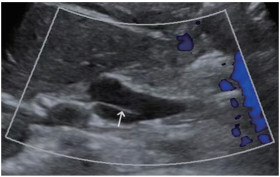

患者出院3个月后,于门诊复查超声,结果提示胆囊管内径约0.47 cm,长度约4.98 cm,肝总管内径约1.09 cm,长度约3.95 cm,胆总管内径约0.87 cm,长度约2.72 cm,胆囊管在肝外胆管下段汇入其内,综上判断为肝外胆管扩张,LICD可能性大(图 2)。结合既往MRCP检查见肝外胆管扩张,胆囊管汇入位置低,汇入点位于胆总管左侧壁(图 3),证实患者为胆囊管低位螺旋汇入。患者因自觉无明显不适,选择定期超声复查。本研究获得我院医学科学伦理委员会批准。

| 肝外胆管扩张. 箭头所示为胆囊管低位汇入,汇入点位于肝外胆管左侧壁. 图 3 3D-MRCP检查图像 |

胆囊管解剖变异的诊断主要借助影像学检查,MRCP是目前胆道解剖学检查中侵入性最小、最可靠的检查方法[8],能全面地显示胰胆管的解剖结构及连接关系,可诊断包括LICD在内的胆管解剖变异[9],有文献[10]报道MRCP诊断胆管解剖变异的准确率高达96.9%。但MRCP对胆管周围组织的定性诊断较差,且易受伪影影响,目前仍不能作为胆道系统疾病的常规检查项目。超声检查是诊断胆道疾病的首选方法,但目前对于LICD的超声诊断报道较为罕见,这可能与未扩张的胆囊管在超声检查中显示困难及超声医生对胆囊管解剖变异认识不足有关。本例患者在既往超声检查中,由于初诊超声医生对LICD认识不足,将相互伴行的胆囊管和肝总管误认为胆总管上段,将胆囊管和肝总管二者相重叠的管壁回声误认为胆总管上段腔内的条带状回声(图 1),而复查超声时发现第一肝门处2条胆管回声,右侧的胆管向上与胆囊相连接,为冗长扩张的胆囊管(图 2A),左侧胆管与肝内的左右肝管相连接,为扩张的肝总管,最终二者汇合成胆总管进入胰头(图 2B),胆囊管在肝外胆管下段汇入,因此,超声诊断为LICD。但超声检查目前很难确定胆囊管汇入点的位置,还需借助MRCP进一步明确。本例LICD患者的3D-MRCP图像可清晰显示胆囊管汇入点位于胆总管的左侧壁(图 3),属LICD的低位螺旋汇入。